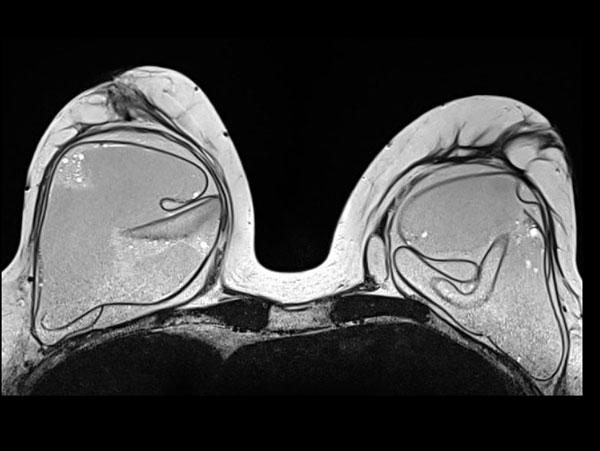

Các nếp gấp hướng tâm là những chỗ gấp vào trong của vỏ túi, kéo dài từ bề mặt vào trong khối gel.

Đây cũng là hình ảnh bình thường.

Phần nội dung bên trong các đường nếp gấp không được chứa Silicone.

Thêm các ví dụ về nếp gấp hướng tâm bình thường.

Đây là thêm các ví dụ về tình trạng gấp vào trong bình thường của vỏ túi.

Không có thành phần silicone bên trong các nếp gấp này.

Một ví dụ khác về đường đi sâu và rộng của các nếp gấp hướng tâm bình thường.